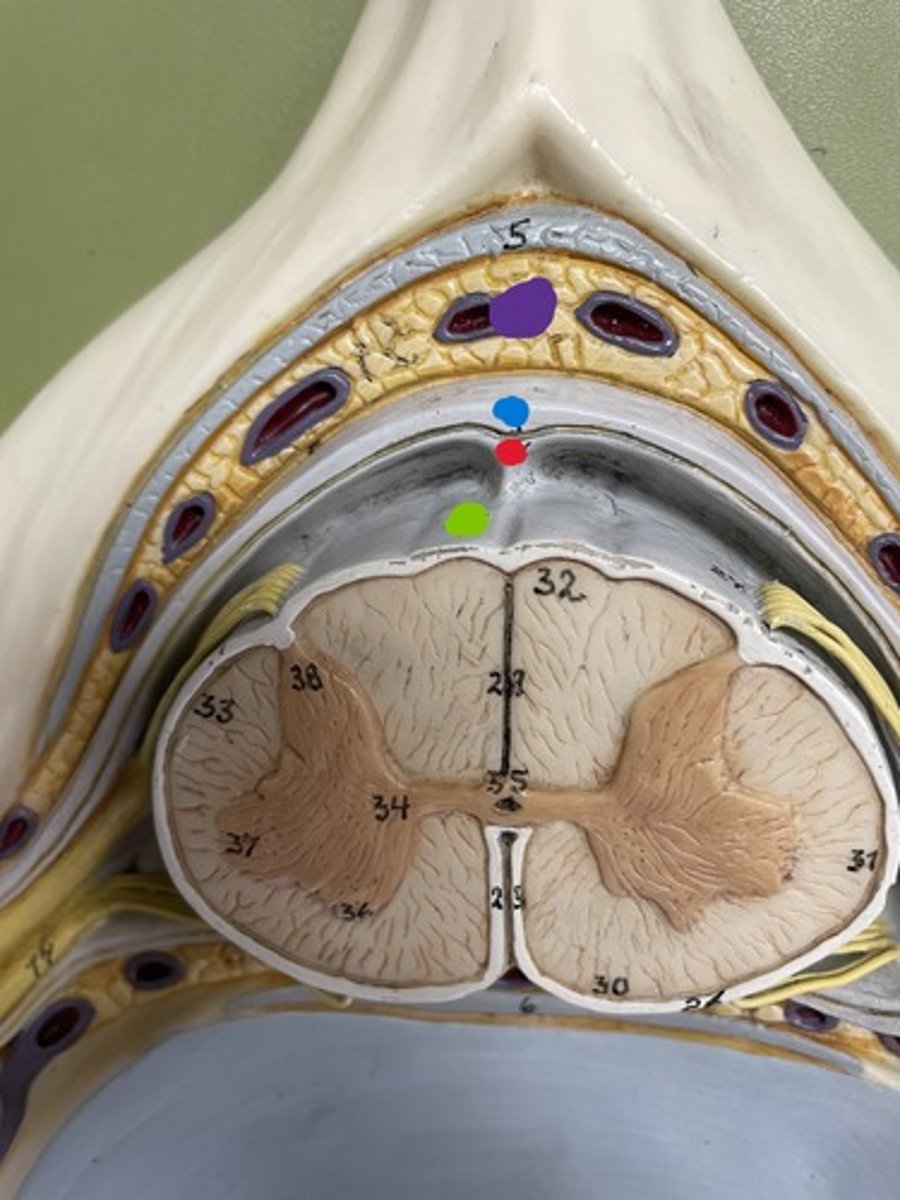

Cervical enlargement

Blue

Lumbar enlargement

Purple

Conus medullaris

Green

Gray matter

Posterior horn

Anterior horn

Lateral horn

G

Gray commissure

gray matter around this structure

Central canal

White matter

Posterior funiculus

Green

Anterior funiculus

Yellow

Lateral funiculus

Red

Posterior median sulcus

green

Anterior median fissure

red

Dura mater

blue

Arachnoid mater

red

Pia mater

green

Epidural space

purple

Subdural space

between red and blue

Subarachnoid space

between red and green